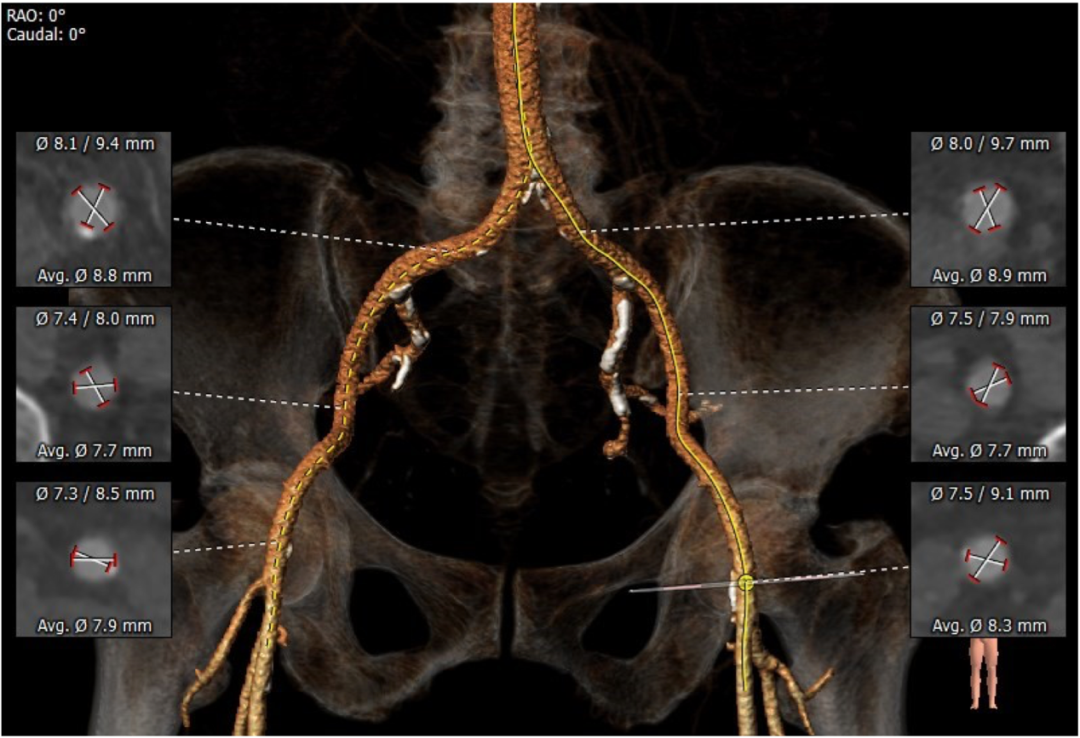

血管外周入路评估

入路血管少量钙化无其他病变,双侧血管内径良好,整体入路血管条件良好。